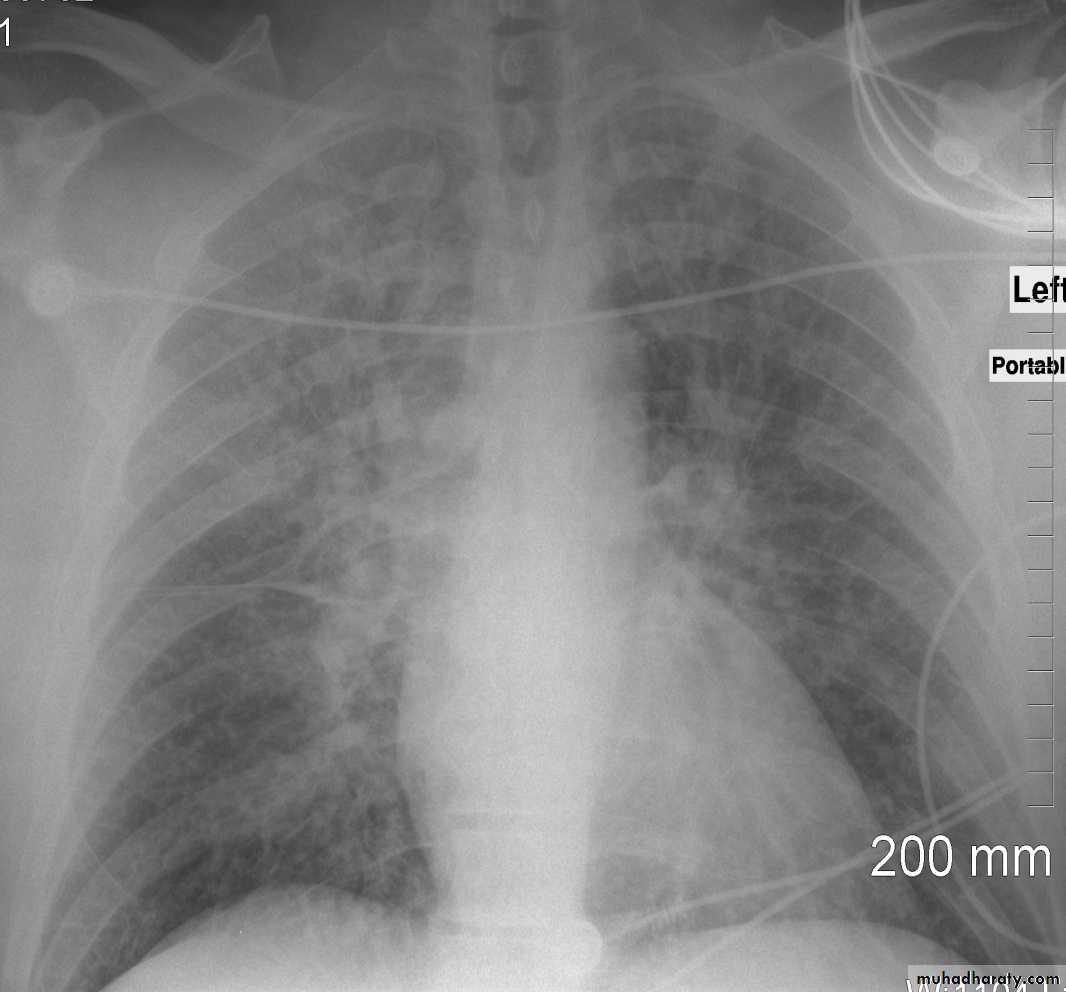

Congestive cardiac failure (CCF) is a form of cardiac failure which is primarily manifested by the heart inability to pump the volume of blood. It can affect the left (common) or right cardiac chambers or both.

Radiographic features

Chest radiograph

With left sided congestive cardiac failure, the features are that of pulmonary edema which includes:

central pulmonary venous congestion ( prominent hilum )

cephalization of pulmonary veins ( upper lobe pulmonary venous diversion )

pulmonary interstitial edema

pulmonary alveolar edema

Cardiomegaly

Pleural effusion